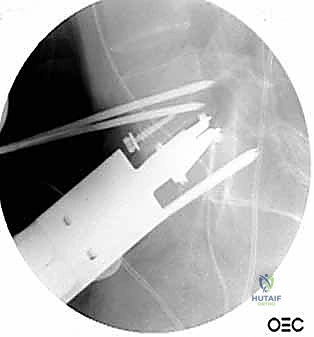

الخطوة 4: التثبيت القوي (Rigid Fixation)

نظراً لضخامة الفراغ الذي تم تعويضه، يتطلب الأمر تثبيتاً قوياً جداً. يتم استخدام شرائح تيتانيوم طويلة ومسامير من الأمام، وفي الغالبية العظمى من الحالات، يتطلب الأمر إجراء مرحلة ثانية لتثبيت العمود الفقري من الخلف بمسامير وقضبان لضمان استقرار البناء الجراحي بزاوية 360 درجة.